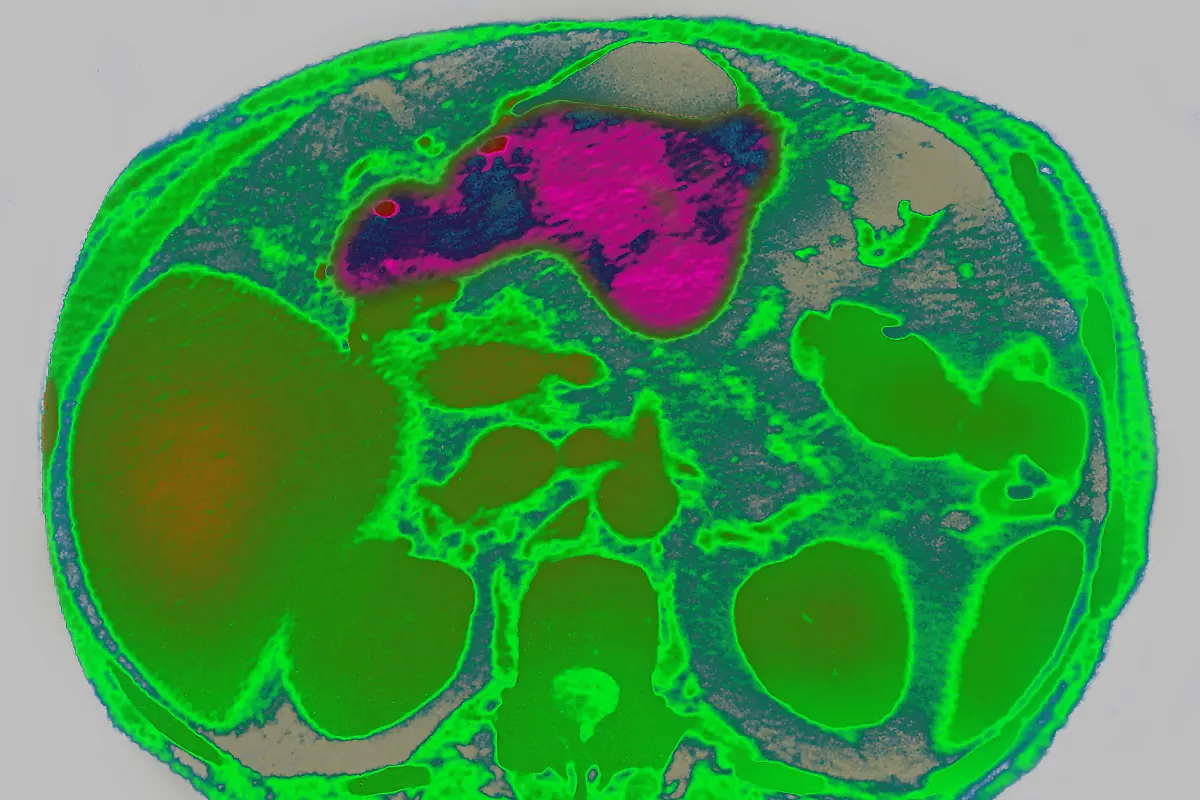

Alkohol, Salz und ZuckerDiese Lebensmittel erhöhen das Krebsrisiko

Eine gesunde Ernährung ist ein wichtiger Baustein zur Krebsprävention und eine bedeutsame Stellschraube. Worauf man beim Essen lieber ganz verzichten sollte und welche Lebensmittel "wahrscheinlich krebserregend" sind - der Überblick klärt auf.